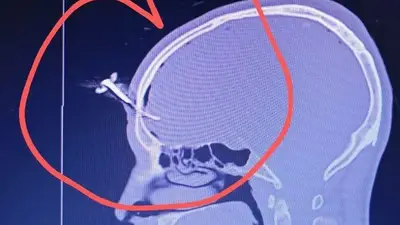

Un violento episodio conmocionó a la comunidad deportiva de Berazategui, Argentina. Durante un partido juvenil en el Club Gimnasia y Esgrima de Villa España (GEVE), una pelea entre padres terminó con un exfutbolista gravemente herido luego de que le clavaran una llave de auto en la cabeza.

La víctima es Jonathan José “El Corto” Smith, de 35 años, exjugador de la Asociación Deportiva Berazategui (ADB). El ataque ocurrió la noche del miércoles durante un campeonato femenino Sub 16. Según testigos, Smith intervino para defender a un amigo que estaba siendo golpeado cuando uno de los involucrados lo atacó con una llave de vehículo.

En redes sociales circularon imágenes del exfutbolista tras el ataque, aunque se conoció que Smith permaneció consciente en todo momento. La investigación continúa y la comunidad deportiva pide justicia y mayores medidas de seguridad en los encuentros juveniles.